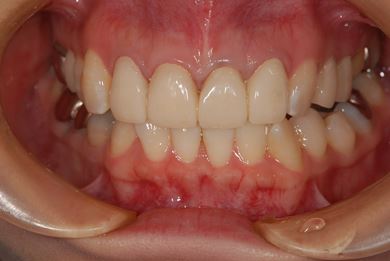

| 性別/年齢 | 女性 / 27歳 | ||||||||||||||||||||||||||||||||

| 主訴 | 審美歯科治療を希望。歯ならびもできるかぎりそろえたい。 | ||||||||||||||||||||||||||||||||

| 治療内容 | オールセラミック4本(オールセラミック用土台4本)、メタルボンドセラミック2本(メタルボンドセラミック用土台2本) | ||||||||||||||||||||||||||||||||

| 総治療費 | 867,825円 | ||||||||||||||||||||||||||||||||

| 治療期間 | 5ヶ月 |